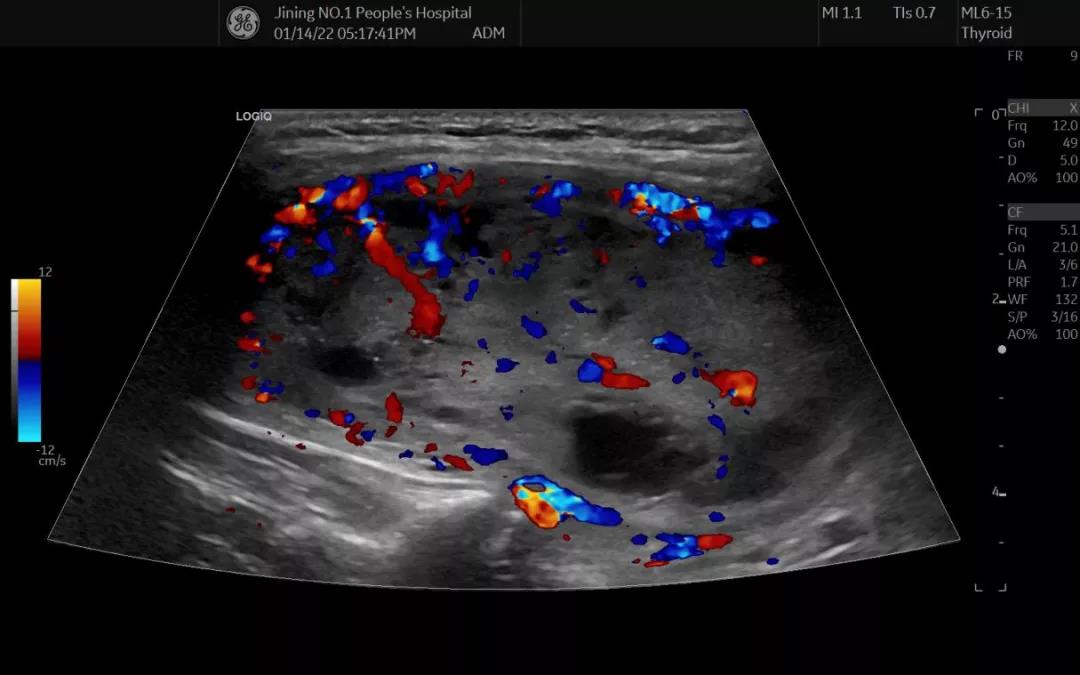

44歲的吳女士,發(fā)現(xiàn)甲狀腺結(jié)節(jié)4個(gè)月,1月前自覺結(jié)節(jié)較之前明顯增大,出現(xiàn)憋悶等不適癥狀來就診。甲狀腺彩超顯示:甲狀腺左葉囊實(shí)性結(jié)節(jié),大小約6.8x4.9x3.1cm,已長至雞蛋大小。經(jīng)過甲狀腺結(jié)節(jié)穿刺術(shù),提取的細(xì)胞學(xué)病理結(jié)果顯示:有較豐富的濾泡細(xì)胞,細(xì)胞未見明顯異型。

手術(shù)中,整個(gè)消融過程順利,術(shù)中及術(shù)后患者無明顯疼痛、無聲音嘶啞、無嗆咳等癥狀,手術(shù)用時(shí)不到30分鐘。術(shù)后,進(jìn)行超聲造影評估,壞死范圍達(dá)到預(yù)期效果,最大程度保留正常的甲狀腺組織,維持患者正常的內(nèi)分泌功能。